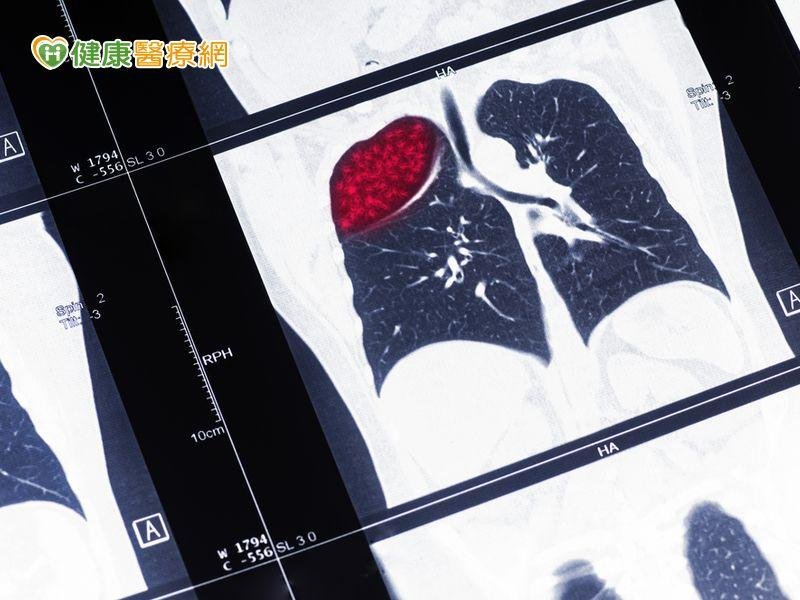

揪出早期肺癌 低劑量電腦斷層幫大忙

約60歲的廖先生,因胃食道逆流就醫。廖先生不抽菸、生活作息正常,但妻子去年因肺癌逝世,因此也擔心自己有罹肺癌風險。電腦斷層檢查,發現左上肺有2顆分別為0.7公分及0.4公分的結節。肺癌為癌症死因冠軍 年奪9千命進行低劑量經診療及手術切除,廖先生切片檢查確診為肺癌第一期,術後規律回診追

>>看全文... 揪出早期肺癌 低劑量電腦斷層幫大忙